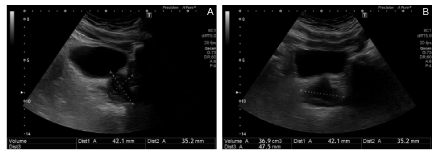

- la prostate (figure 25.1) :

Fig.25.1. Échographie pelvienne par voie sus-pubienne avec mensurations prostatiques.

Plan de coupe sagittal (A). Plan de coupe axial (B). Hypertrophie prostatique modérée diffuse (volume estimé à 37 cm3), paroi vésicale régulière, pas de soulèvement du plancher vésical.

Source : CERF, CNEBMN, 2022.

– mesure du volume prostatique ;

– type d’hypertrophie (diffuse ou lobe médian avec protrusion intravésicale) ;